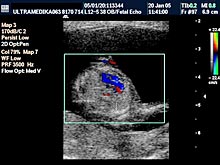

D) Četvrti UZ marker koji mora biti proveren je procena PI (pulzativnog indeksa) tj. procena otpora proticanju krvi kroz venski sud koji dovodi krv u srce ploda i naziva se Duktus venozus! Ova struktura je veličine nekoliko milimetara i pouzdano se može kodirati Braund Band CD i kolor Power Dopplerom. Praktično samo aparati velikih mogućnosti koji koriste ovu tehniku mogu u velikom procentu tj kod većine trudnoća u ovoj gestacionoj starosti registrovati patološki protok u Duktusu venozusu!

Inače patološki protok u ovom malom krvnom sudu je od velikog značaja jer može ukazivati da plod ima hromozomsku anomaliju ili urođenu srčanu manu!

Procena srca se ogleda u proceni položaja srca, proceni anatomskih karakteristika sve 4 srčane šupljine tj. određivanje njihovog adekvatnog položaja, proceni položaja AV valvula, proceni postojanja AV kanala, adekvatnom položaju aorte i plućne arterije, i odnos velikih krvnih sudova na odgovarajućim presecima tj. 3VV i 3 VT. Često je i venska drenaža dostupna pregledu. Procena toka krvi je moguća aparatima koji mogu kodirati oskudan protok kroz srce u ovoj gestacionoj starosti. Adekvatno prikazivanje prolaska krvi kroz srce nije moguć bez postojanja Broad band CD i kolor Power Dopplera.